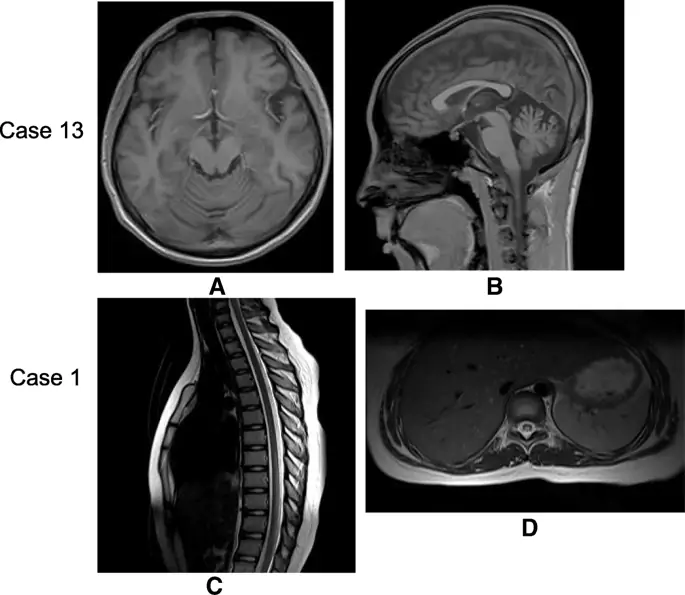

При обнаружении нейровизуализации преобладали церебральная атрофия различной степени (11/16), за которой следовали высокоинтенсивные поражения белого вещества (4/16), поражения мозжечка (1/16), атрофия мозжечка (1/16) и поражения спинного мозга. (1/16). Были также 2 пациента с нормальной визуализацией (Таблица 2). В отличие от диффузного набухания белого вещества в ранних случаях cblC, поражения белого вещества в этих поздних случаях представлены двусторонними симметричными пятнистыми повреждениями, главным образом в центральном яичнике, лучистой короне и перивентрикулярной области (Fig. 1a-d). Случай 8 представил только небольшие поражения в односторонней задней желудочковой области (Fig. 1e, f). Поражения мозжечка редко сообщалось в случаях cblC. В этом исследовании двусторонние поражения коры мозжечка были обнаружены в одном случае (впервые сообщалось в нашем предыдущем докладе (8)) и атрофия мозжечка в случае 13 (Fig. 2a, b). МРТ спинного мозга показала повреждения спинного мозга в случае 1 (рис. 2в, г), и после лечения повреждения исчезли. Ни в одном из случаев не было выявлено поражений базальных ганглиев, гидроцефалии или разбухания диффузного белого вещества, которые были общими признаками при раннем начале заболевания кобаламином С. Только в случае № 4 имелись данные МР-спектроскопии из областей двустороннего поражения центрального яичника и короны, которые показали снижение пика N-ацетиласпартата (NAA) и увеличение пика холина (Cho) и лактата (Lac) в очагах поражения с обеих сторон.

фигура 2

Атрофия мозжечка и поражения спинного мозга при поздней стадии заболевания ХБС. МРТ головного мозга случая 13 в таблице 1 показала атрофию мозжечка на взвешенном изображении Т1 (а: поперечный разрез, б: сагиттальный разрез). МРТ спинного мозга в случае 1 в таблице 1 показала поражения спинного мозга в T8-11. Повреждения представляли гиперинтенсивность на взвешенном изображении T2 (c: сагиттальный разрез, d: поперечный разрез)

Изображение в полном размере